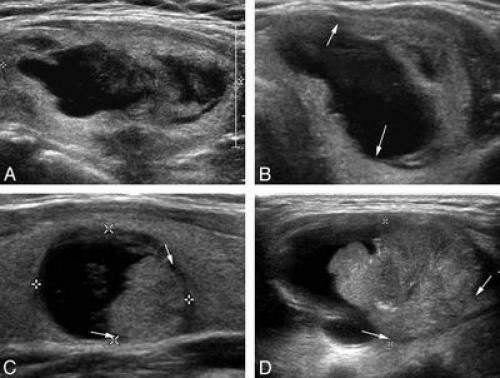

Чем отличается узел от кисты щитовидной железы. УЗИ кистозного узла щитовидной железы

Чем отличается узел от кисты щитовидной железы. УЗИ кистозного узла щитовидной железы.

1. Типичные варианты:

• Коллоидная киста

• Гиперпластический узел

• Геморрагическая киста

2. Менее типичные варианты:

• Папиллярный рак

• Острый гнойный тиреоидит

3. Редкие, но важные варианты:

• Фолликулярный рак

• Врожденная киста

(Справа) УЗИ, продольная проекция: множественные артефакты в виде «хвоста кометы», сгруппированные и вплотную прилежащие к перегородкам и дебрису в коллоидном узле.

(Справа) УЗИ, продольная проекция: визуализируется узел щитовидной железы, напоминающий губку. Кистозный компонент узла составляет >50%. Визуализируются перегородки. Картина патогномонична для доброкачественного образования.

(Справа) КТ с КУ. Аксиальная проекция: визуализируется кистозно измененный узел щитовидной железы, распространяющийся в средостение. КТ позволяет лучше оценить каудальное распространение больших узлов. Была выполнена аспирация, обнаружились продукты деградации крови.

(Справа) Энергетическая допплерография, продольная проекция: в этой же области определяется хаотическая интранодулярная васкуляризация, сопоставимая с папиллярным раком щитовидной железы. УЗИ используется для направления иглы к солидной части образования при ТАБ.